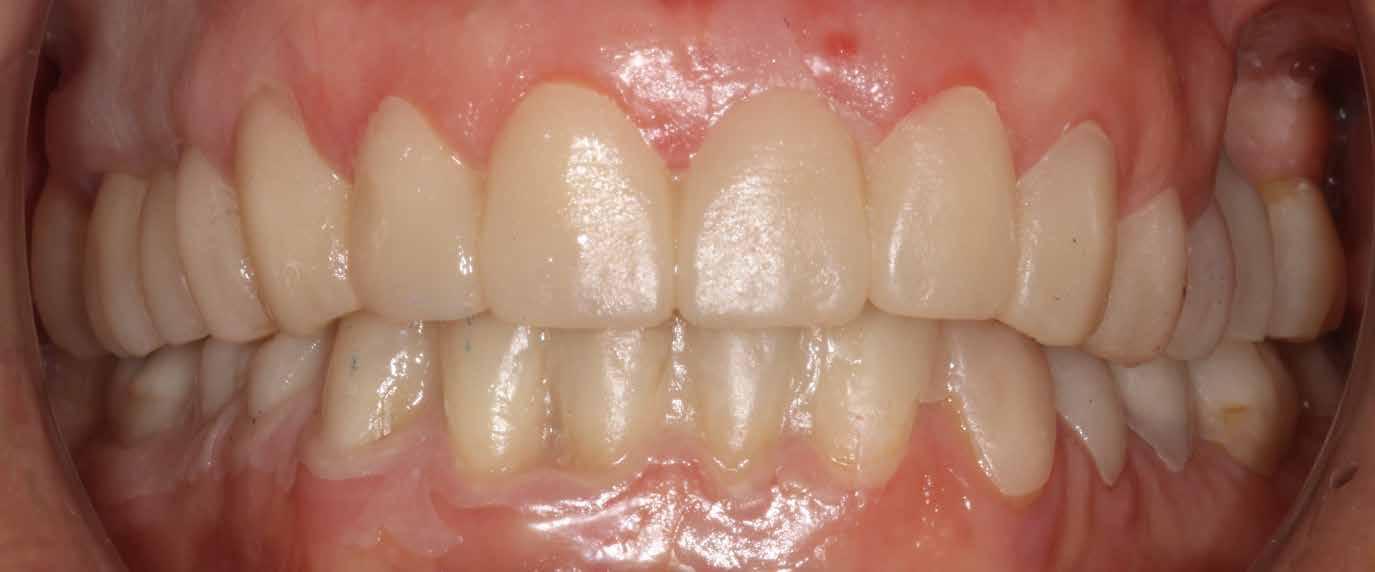

2015-ben egy 47 éves férfi páciens állkapocs-ízületi panaszai miatt kereste fel a rendelőnket. Ezen felül esztétikai problémát jelentett számára, hogy az egyik felső nagymetszőfogán lévő héj eltört (1-3. ábrák). A klinikai és radiológiai vizsgálatot követően megállapítható volt, hogy a páciens kifejezett bruxizmusa miatt csökkent a harapási magassága, és jelentős mennyiségű saját foganyagot abradált el (4. ábra)

Szájterpesz használata mellett digitálisan intraorális fotók készültek a páciensről mind frontális, mind laterális és okkluzális irányokból. További fotók is készültek a páciensről egy digitális tükörreflexes kamera segítségével (frontális és laterális irányból, valamint 45 o-os szögből). Mindkét állcsontról digitális lenyomat készült egy intraorális szkenner segítségével (Care stream 3500). A maximális-interkuszpidációs helyzetet (IKP) szintén a Carestream 3500-as készülék felhasználásával rögzítet -